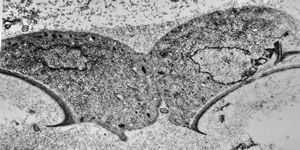

Giardia (Lamblia) intestinalis